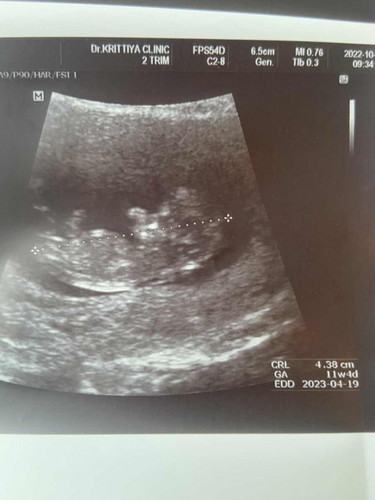

ท้องที่3แล้วค่ะ ผู้ชายทั้งสอง วันนี้ไปฝากท้อง คุณหมอทักว่ามีแหลมๆนะ น่าจะชาย3รึเปล่า เพิ่ง 11วีคค่ะ แต่คุณหมอทักดับฝันแม่ซะแล้ว อยากมีลูกสาวกับเขาบ้างพอจะมีหวังไหมน้อ แม่ๆบ้านไหนหมอทักแบบนี้บ้างคะ